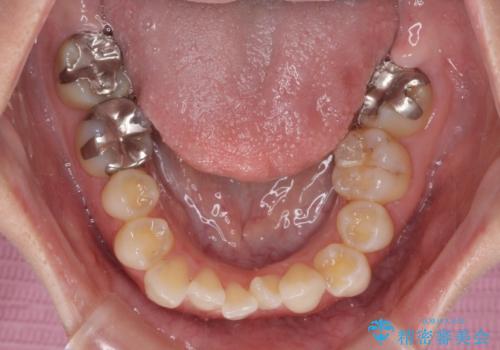

- 左上の八重歯と前歯のデコボコを気にして来院された患者様です。

下顎が左側にズレており、下顎前歯は1歯欠損していたため、左上小臼歯1本を抜歯し、ワイヤー装置にて矯正治療を行うこととしました。